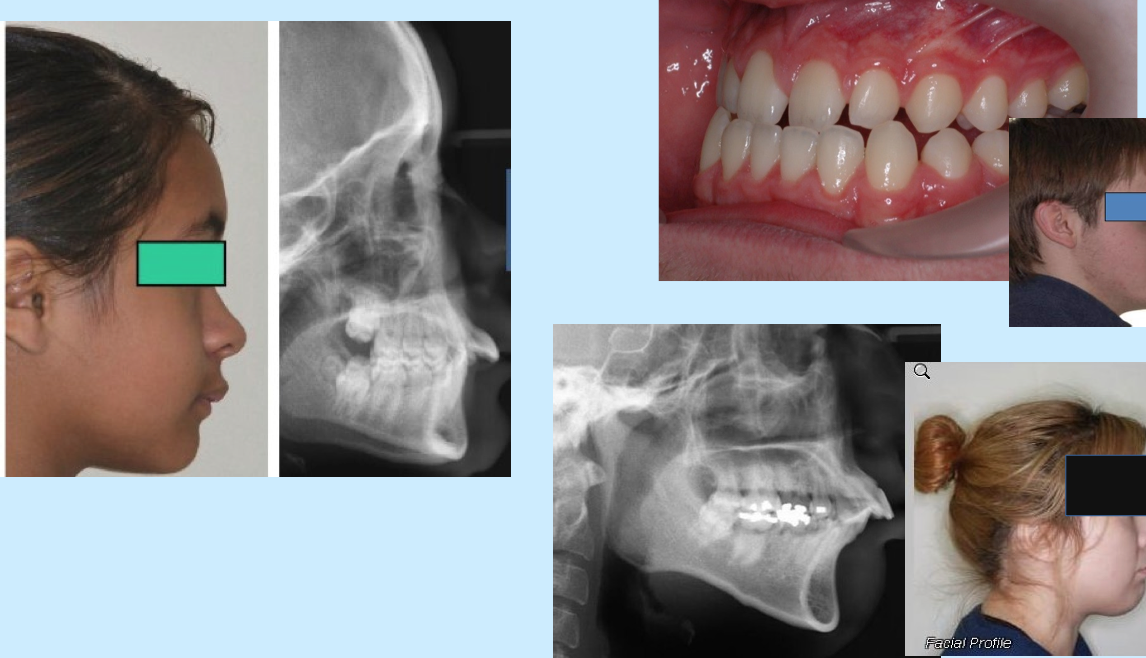

2-skeletal class 2

2-retrognathic mandible & prognathic maxilla

skeletal class 1

skeletal class 2